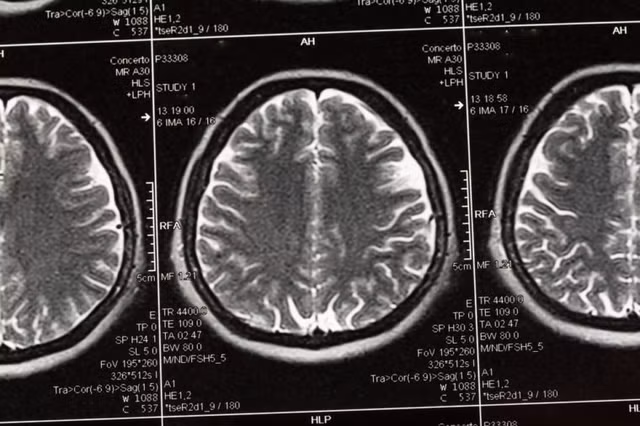

Nghiên cứu trên Tạp chí y khoa The New England Journal of Medicine đã chỉ ra rằng người nặng gần 70 kg (154 pound) đốt cháy 21 calo trong 6 phút làm “chuyện ấy”. Dù không hiệu quả như bài đạp xe trong phòng tập nhưng việc "yêu" trong nửa tiếng có thể giúp đốt cháy khoảng 100 calo.